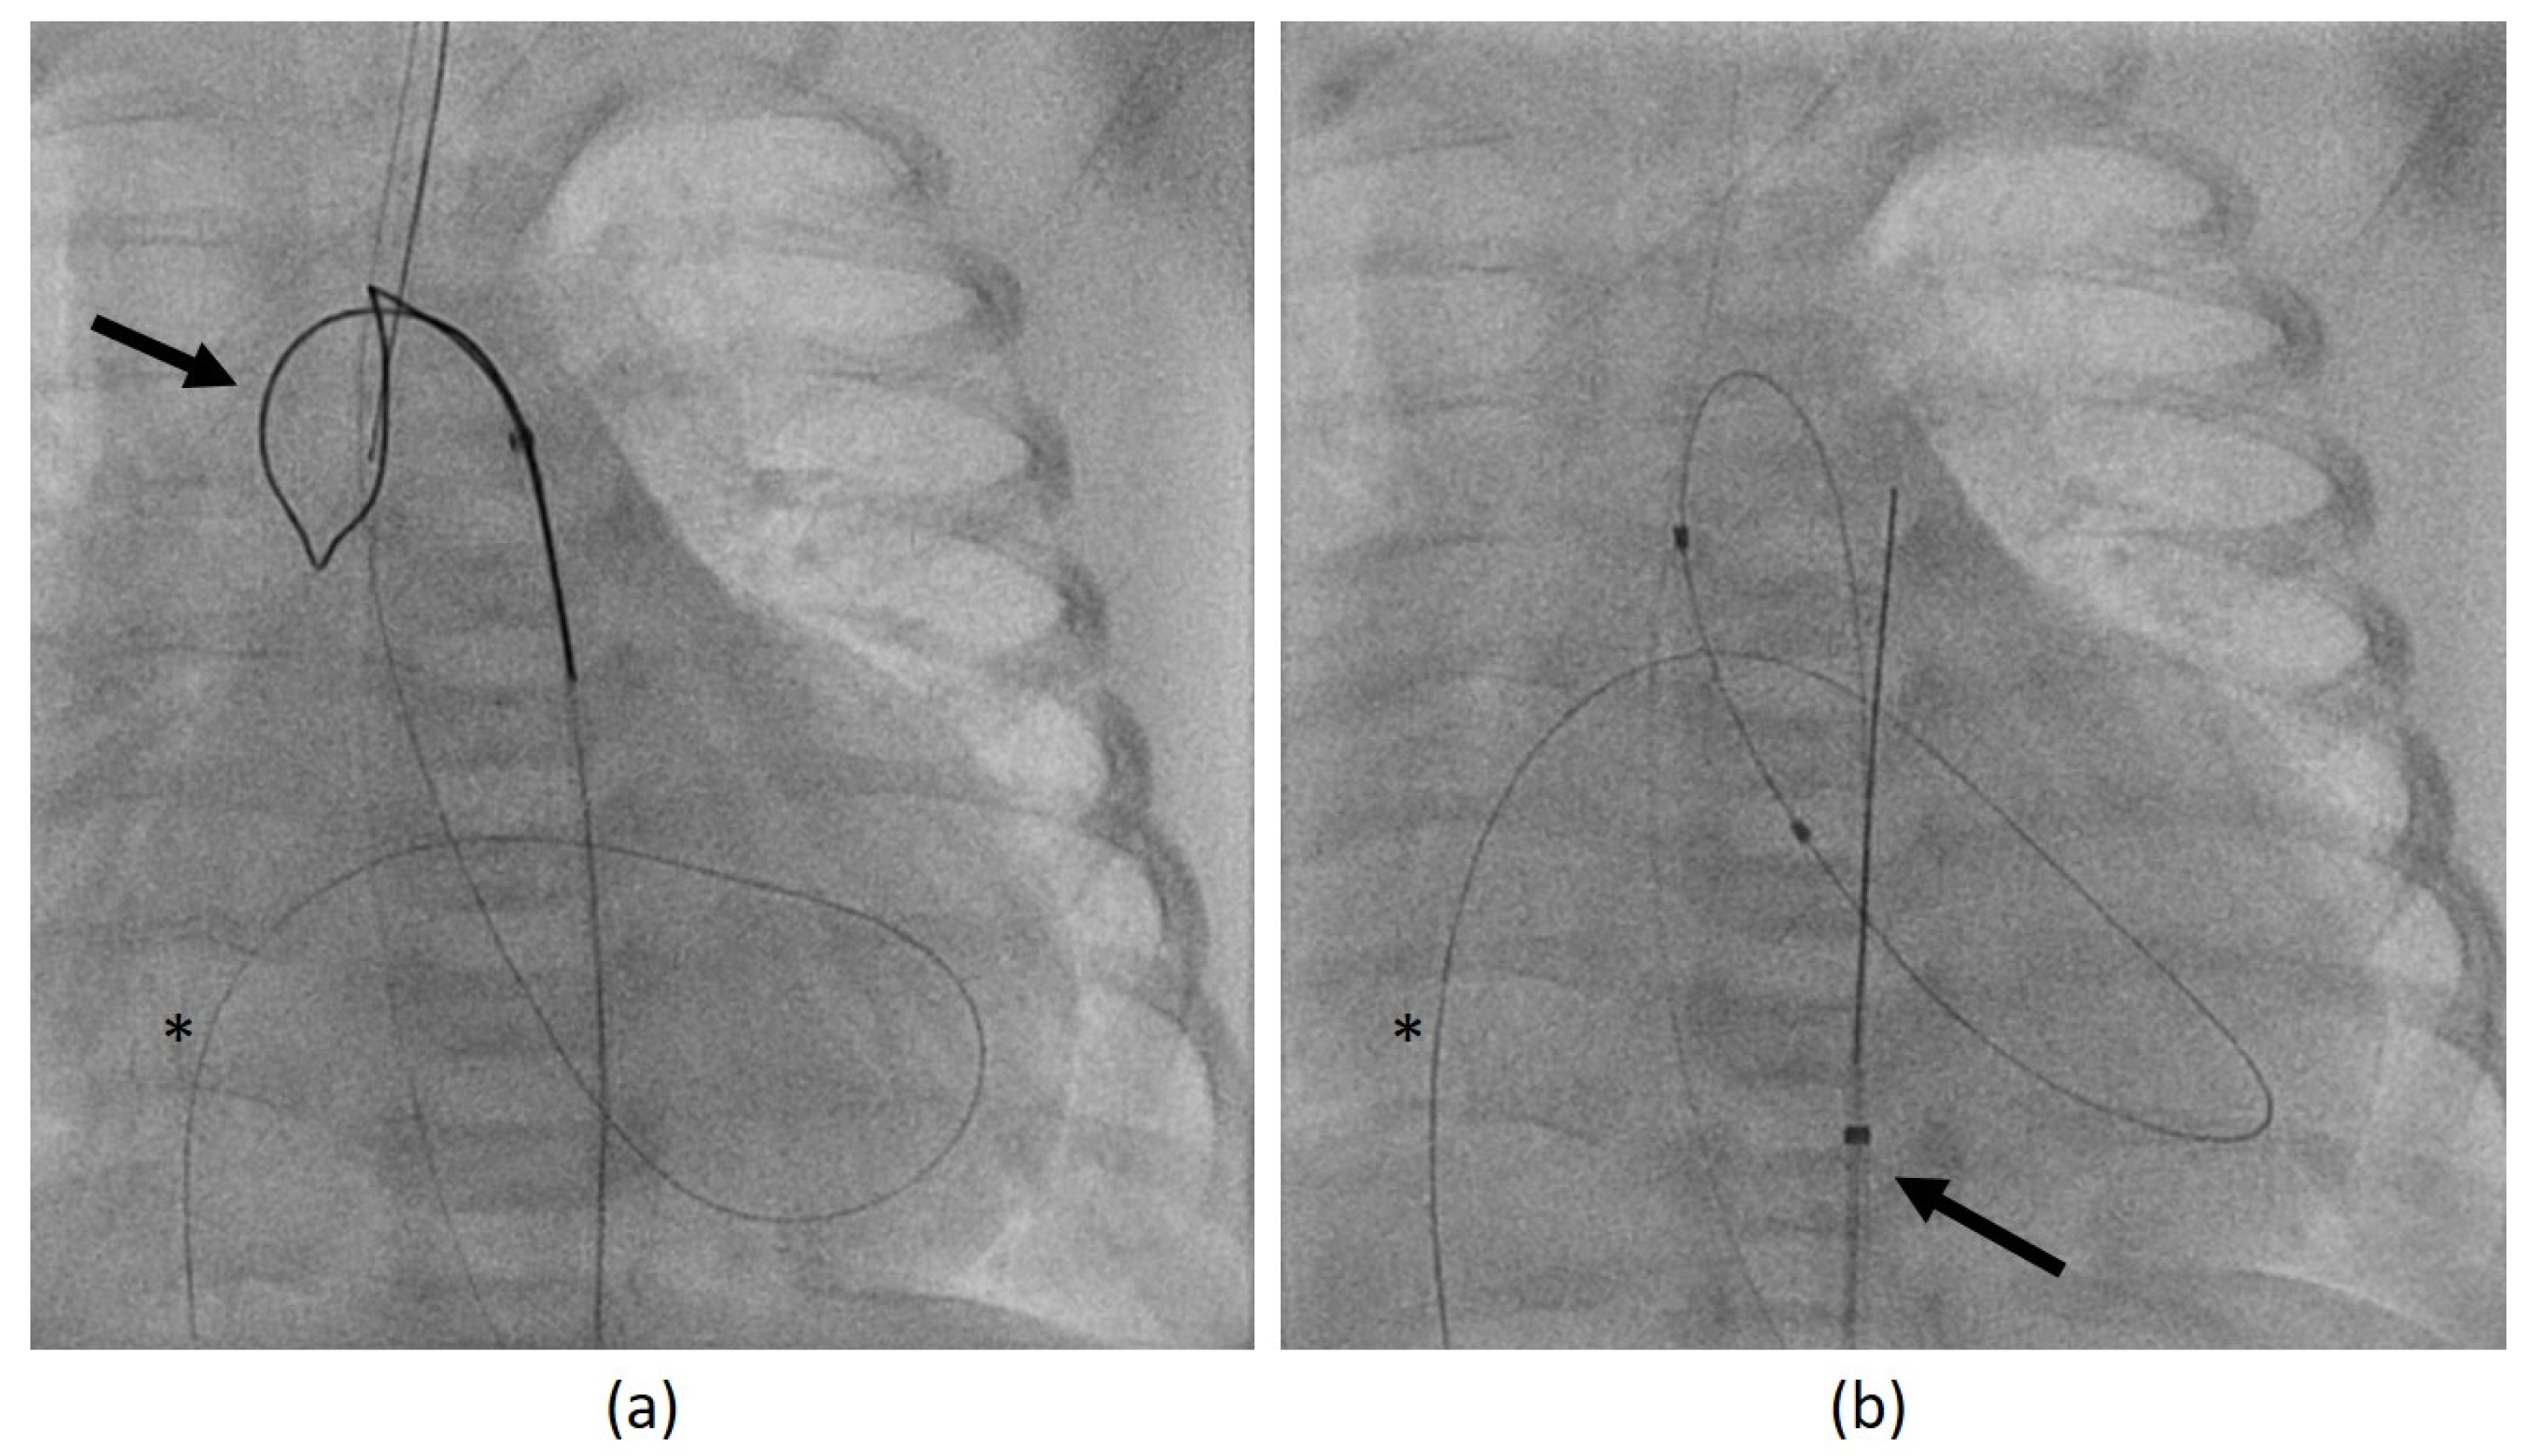

3.3.2. Miscellaneous Complications

• In case 2, there was an air embolism into the left ventricle during the patient’s first catheterization. Due to the depressed LV function with low contractility, the air bubble remained ventrally in the LV (Figure 7) where we managed to extract it by the catheter.

Figure 7. Angiographic image, lateral view. Air bubble (arrow) ventrally in the left ventricle during catheterization. The asterisk marks an angiographic catheter.